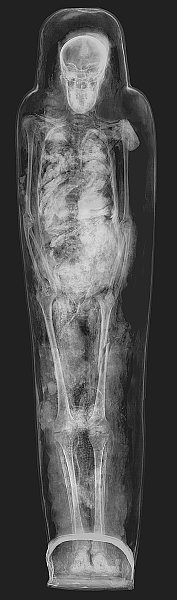

Mumienhülle mit Mumie der Hausherrin Nes-chons

Röntgenbild

Spätzeit, 25. Dynastie, 8. Jh. v. Chr.

Vermutlich aus Theben

Leinen, Stuck, Bemalung,

Menschenmumie L. 154,5 cm, Br. ca. 38 cm

Kunsthistorisches Museum Wien, Ägyptisch-Orientalische Sammlung